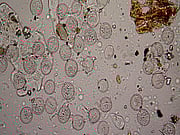

Prueba analítica

Una biopsia es un procedimiento en el que se extrae una muestra de tejido del cuerpo para su examen. El diagnóstico se establece cuando las células se examinan al microscopio. La prueba suele centrarse en encontrar células anómalas que pueden proporcionar datos que indiquen que existe una inflamación o un trastorno, como el cáncer. Los tejidos que suelen examinarse son muestras de piel, mama, pulmón, hígado, riñón y hueso.